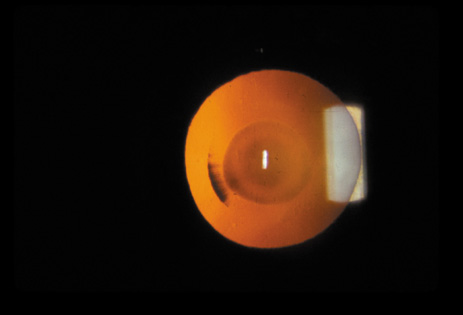

Nuclear cataracts tend to progress slowly. The refractive index of the lens changes as the nucleus progressively hardens, which usually results in increasing myopia.20,21 In some patients this is accompanied by optical distortion, especially of distant images, while near vision remains unaffected. A nuclear cataract is best seen with the narrow-beam direct illumination employed by the slit-lamp, which reveals the color and generalized haze or opalescence of the nucleus. In the early stages, the two halves (cotyledons) of the embryonic nucleus remain visible (Fig. 3). Later the entire nucleus appears as a homogeneous mass in contrast to the cortex (Fig. 4). Retroillumination may show the “oil droplet” effect (Fig. 5). Sometimes one may notice crystals in the lens nucleus (known as a Christmas tree cataract; Fig. 6A and B).

Fig. 3. Early nuclear cataract. Note the “cotyledons” in the nucleus.

Fig. 4. Advanced nuclear cataract. Note the homogeneous nuclear opacity.

Fig. 5. “Oil droplet” appearance of a pure nuclear cataract seen on retroillumination examination.